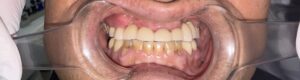

写真をご覧ください。

真ん中2本の歯のない所に、両横から橋を伸ばして6本の歯を作ります。

お口にセットしますと、にっこり笑っても違和感のないお口になります。

もちろん、ちゃんと噛み切れます。

前歯のブリッジです。自然で、よく噛めるようになられました。